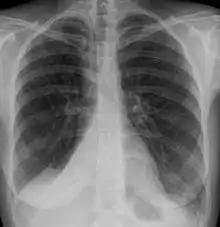

- الأشعة السينية للصدر (اعتِتَمام الرئة المصابة و تقلص حجمها)

أشعة الصدر السينية كافية لتشخيص حالات الانخماض المعتدة اكلينيكياً. الانخماص ما بعد العمليات الجراحية يظهر في الجزء الأدنى من الرئتين.